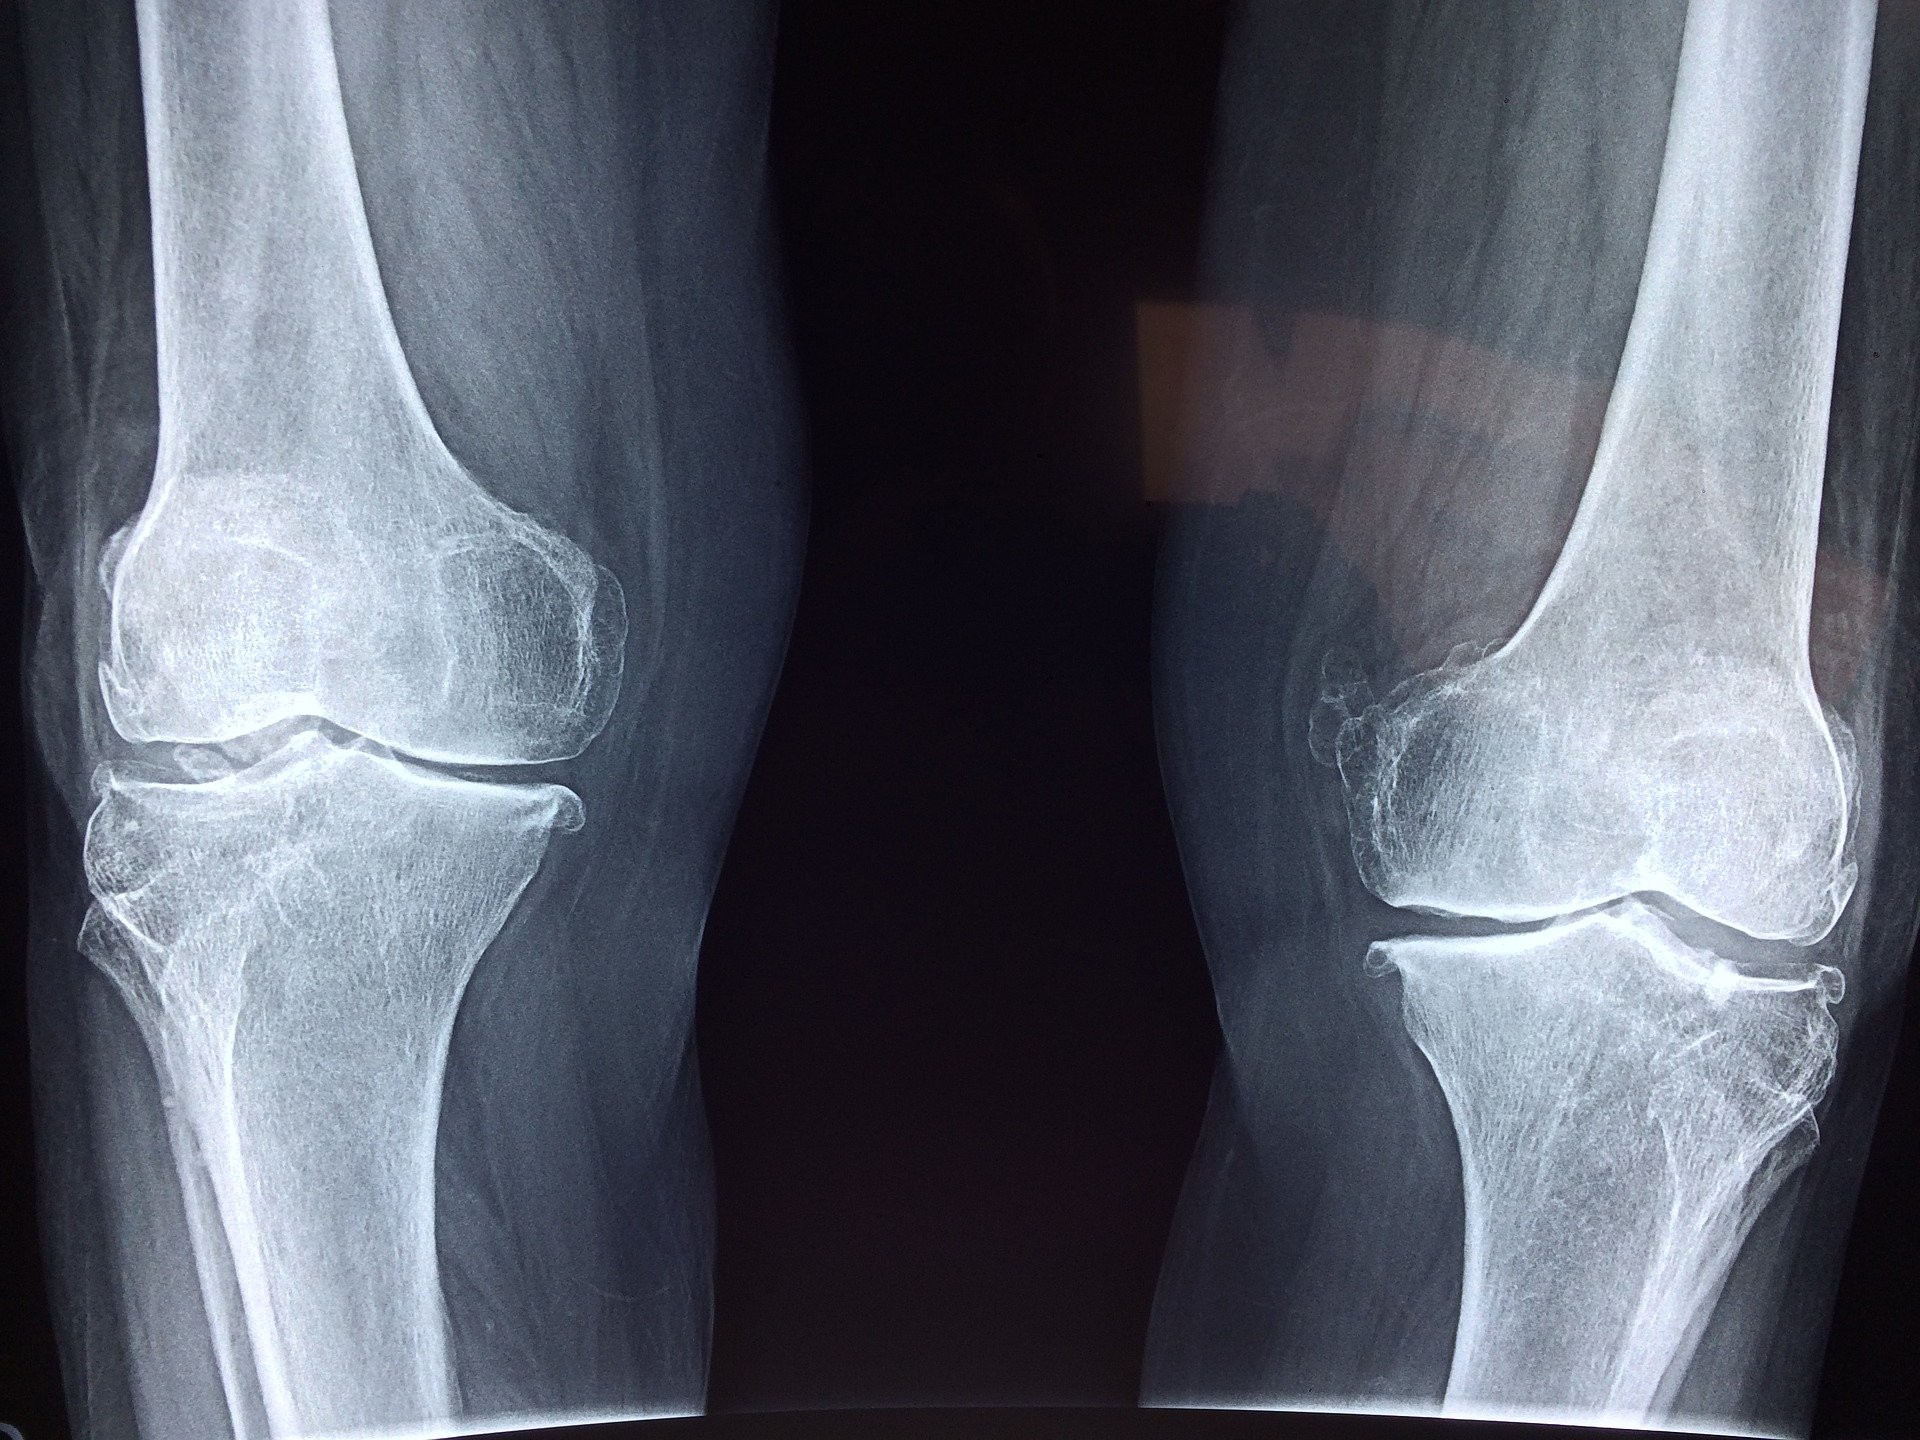

Więc jak radzić sobie, gdy kolano boli, puchnie, a do lekarza daleko?

Często ignorujemy nasze problemy zdrowotne, dając sobie dodatkowe dni na sprawdzenie, czy „to coś poważne”. Ale co, jeśli te dodatkowe dni kompletnie utrudniają nam życie, a terminy u lekarza nie są takie szybkie, jakbyśmy chcieli?

Oto kilka sprawdzonych metod na pozbycie się bólu i obrzęku.